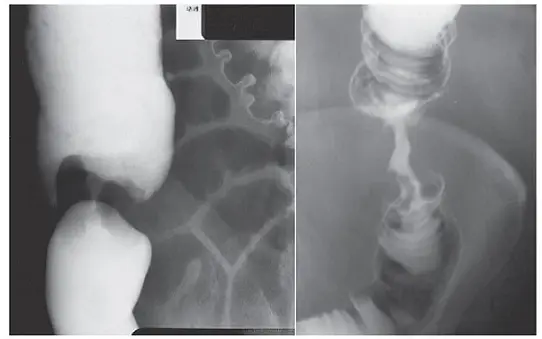

患者接受大腸鋇劑灌腸(barium enema)攝影的結果如下圖,最可能是下列何種疾病?

題目提供的兩張大腸鋇劑灌腸攝影影像(左圖為腸道較長區段全貌,右圖為不同視角或局部放大),均顯示了極為經典的蘋果核徵象(Apple-core sign):

- 局部環狀狹窄(Circumferential narrowing):可見一段腸腔出現極度不規則、且明顯變窄的通道(常被稱為癌性隧道)。

- 肩狀邊緣(Shouldering margins / Overhanging edges):在狹窄段的近端與遠端,正常擴張的腸管與病灶交界處呈現突兀的、宛如大陸架般的懸垂邊緣。

- 黏膜破壞(Mucosal destruction):狹窄段內的邊緣呈現不規則與僵硬,顯示正常腸黏膜已被破壞。

綜合以上特徵,影像呈現如同被咬剩的「蘋果核」,這是環狀生長(Annular growth)的腫瘤侵犯腸壁的典型表現。